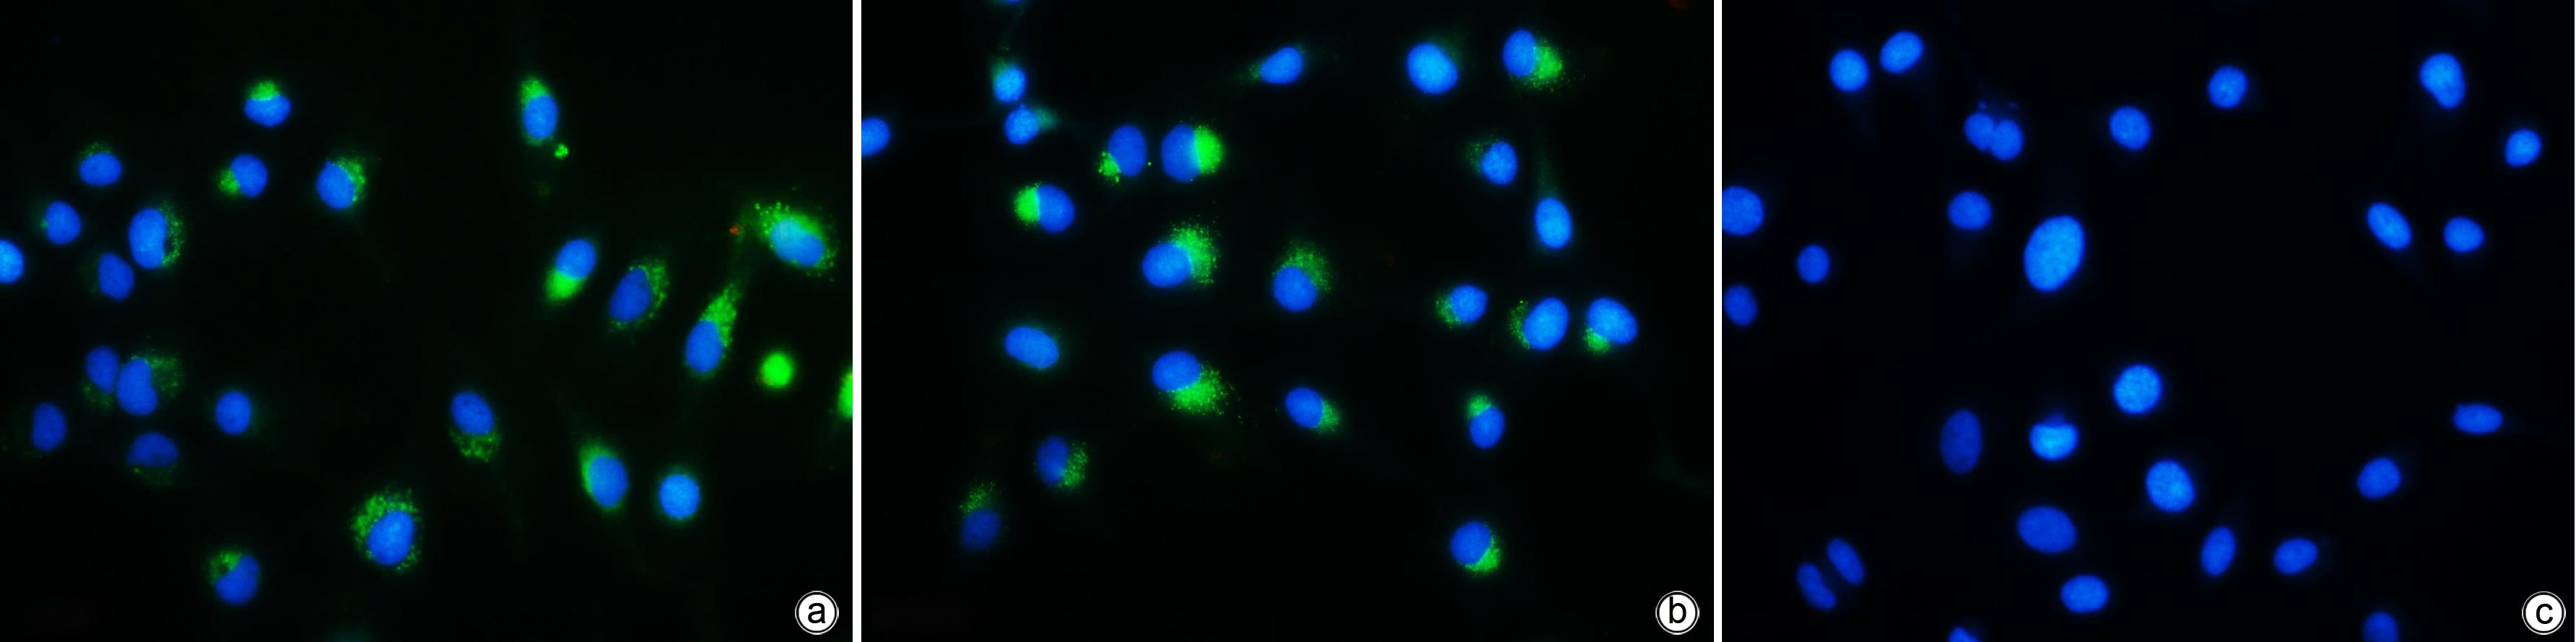

细胞毒性T淋巴细胞来源外泌体抑制肝星状细胞活化的机制

覃川福, 赵雅丽, 龙丽娟, 邱华

2023, 39(10): 2340-2347. DOI: 10.3969/j.issn.1001-5256.2023.10.011

摘要(907) HTML (365) PDF (1118KB)(71)

目的  探讨细胞毒性T淋巴细胞(CTL)来源外泌体能否下调HBx表达从而抑制肝星状细胞(HSC)活化。  方法  收集HepG2、HepGA14、CTL细胞上清液提取外泌体(分别简写为NC-exo、HBV-exo、CTL-exo),透射电镜观察其形态,Western Blot检测外泌体标志物CD63和TSG101的表达。将氟硼二吡咯染料(BODIPY)标记的NC-exo、HBV-exo以及CTL-exo与HBV-exo按不同比例混合后,分别与HSC LX-2(HSC-LX2)共培养,荧光显微镜观察外泌体能否进入LX-2细胞,倒置显微镜观察细胞形态学改变,实时荧光定量PCR (qPCR)检测LX-2细胞中TGF-β1、α-平滑肌肌动蛋白(α-SMA)、Ⅰ型胶原蛋白(Collagen1)等活化生物标志物的表达。将CTL-exo加入到HepGA14培养体系中,qPCR检测HepGA14细胞内HBV DNA、cccDNA及外泌体中HBx mRNA表达水平,Western Blot检测外泌体HBx蛋白表达水平。符合正态分布的计量资料两组间比较采用成组t检验,多组间比较采用单因素方差分析,进一步两两比较采用LSD-t检验。  结果  外泌体均为双层膜结构的微囊,呈圆形或椭圆形,囊泡的直径为50~100 nm,表达标志性蛋白CD63和TSG101。荧光显微镜观察示外泌体可进入LX-2细胞,并且HBV-exo进入LX-2细胞后,HSC胞体增大、胞突伸展。qPCR结果示NC-exo、HBV-exo、NC-exo+HBV-exo和Con组LX-2细胞中TGF-β1、α-SMA、Collagen1基因表达水平差异均有统计学意义(F值分别为444.678、417.144、571.508,P值均<0.05)。CTL-exo干预HepGA14细胞后,qPCR结果显示HepGA14细胞中HBV DNA、cccDNA表达水平较对照组明显下降(P值均<0.05),外泌体中HBx mRNA相对表达量明显下降(P<0.05);HBx蛋白表达水平与对照组相比也明显下降,差异有统计学意义(P<0.05)。CTL-exo和HBV-exo按照不同比例(2∶1、5∶1、10∶1)进行混合后干预LX-2细胞,qPCR结果显示各组间LX-2细胞中TGF-β1、α-SMA和Collagen1基因表达随着CTL-exo比例的增加而逐渐减弱,差异有统计学意义(P值均<0.05)。  结论  CTL-exo可下调HBV-exo中HBx蛋白表达抑制HSC活化,提示CTL-exo有抗乙型肝炎肝纤维化作用。